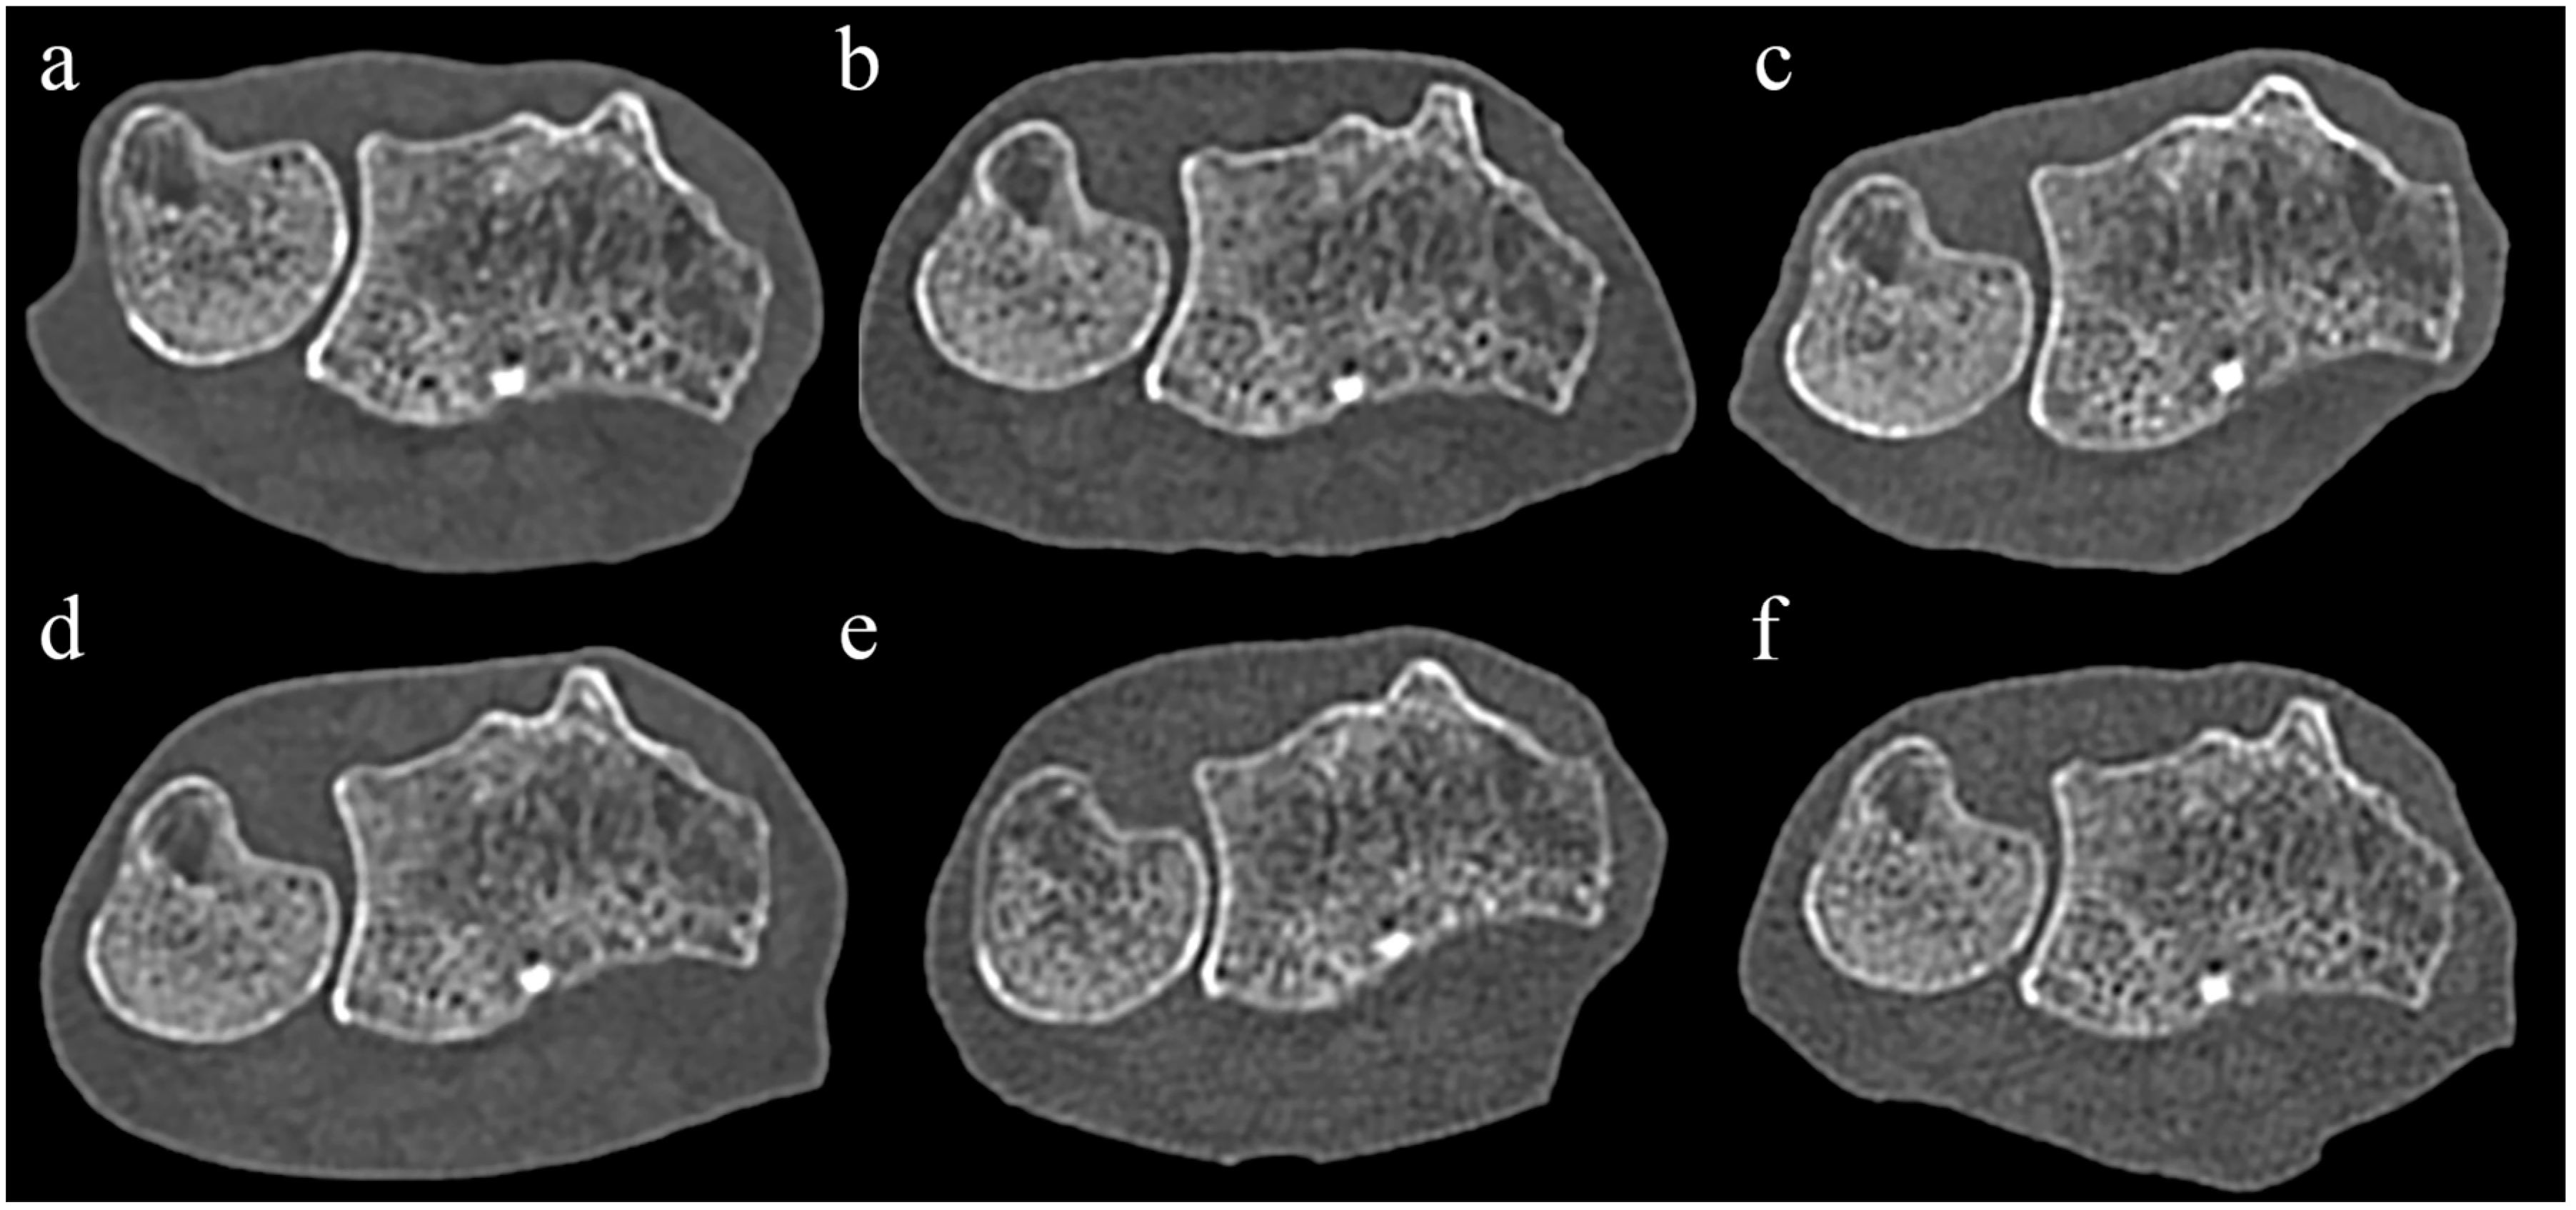

Even in UHR mode, there was no significant difference in the score for the visibility of trabecular bone between PCCT and all EIDCTs, and there was also no significant difference in the visibility of cortical bone with three EIDCTs (Figure 2 and Table 5). In contrast, PCCT had significantly higher scores of image quality than three EIDCTs in STD mode and all EIDCTs in UHR mode.

Figure 2. Comparison of PCCT and EIDCT images in ultra-high-resolution (UHR) mode. Images were obtained using (a) Alpha, (b) Drive, (c) X.cite, (d) Force, (e) AS, and (f) Flash scanners. Qualitative scores for all images were obtained by using the image in Figure 1b as a reference. Although the appearance of cortical bone and trabecular bone in each image is similar, the PCCT image (a) has significantly less noise than the EIDCT images (bf).